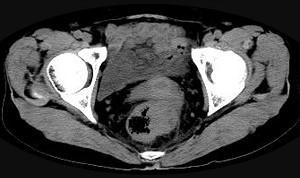

问题 男,56岁,排便形状改变,便不尽感,CT检查如图所示,下列说法正确的是 ( )

选项 A、此为直肠息肉 B、此为直肠癌 C、其表面光滑,边界清楚 D、肠腔未见狭窄 E、肠壁上有蒂状新生物

答案 B